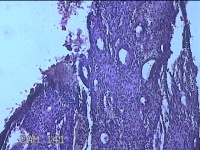

宫腔内容物

性别

女

年龄

38岁

临床诊断

稽留流产

一般病史

停经2月,阴道流血2天。

标本名称

大体所见

灰白暗红色不规则组织6.5x2x1.3cm一块,内有少许绒毛样组织。